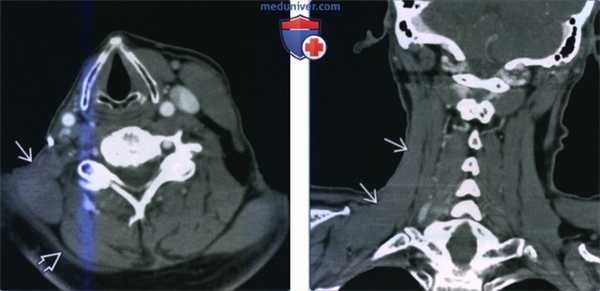

(Слева) КТ с КУ, аксиальная проекция, пациент, несколько месяцев назад перенесший радикальную шейную лимфодиссекцию. Справа определяется гипертрофия мышцы, поднимающей лопатку. Внутренняя яремная вена и грудино-ключично-сосцевидная мышца слева нормальные. Трапециевидная мышца атрофирована.

(Справа) КТ с КУ, аксиальная проекция. Параганглиома яремного отверстия (не показана) стала причиной гипертрофии мышцы, поднимающей лопатку, и атрофии трапециевидной и грудино-ключично-сосцевидной мышц. Также имеется атрофия языка с его жировой инфильтрацией.

(Слева) КТ с КУ, аксиальная проекция. Гипертрофия правой мышцы, поднимающей лопатку. Обратите внимание, что при радикальной шейной лимфодиссекции правые грудино-ключично-сосцевидная мышца и внутренняя яремная вена были удалены. Трапециевидная мышца атрофирована вследствие повреждения добавочного нерва в ходе операции.

(Справа) КТ с КУ, сагиттальная проекция. Мышца, поднимающая лопатку, гипертрофирована на всем протяжении. Плотность мышцы нормальная.